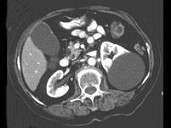

- 多项选择题女,38岁, 左腰部胀痛不适,CT平扫+增强如图所示, 下列说法正确的是 ( )

A、平扫时可见左肾一类圆形囊性病灶

B、病灶边界清晰,表面光整

C、增强扫描皮质期和实质期该病灶均未见强化

D、考虑为左肾囊性肾癌

E、考虑为左肾囊肿